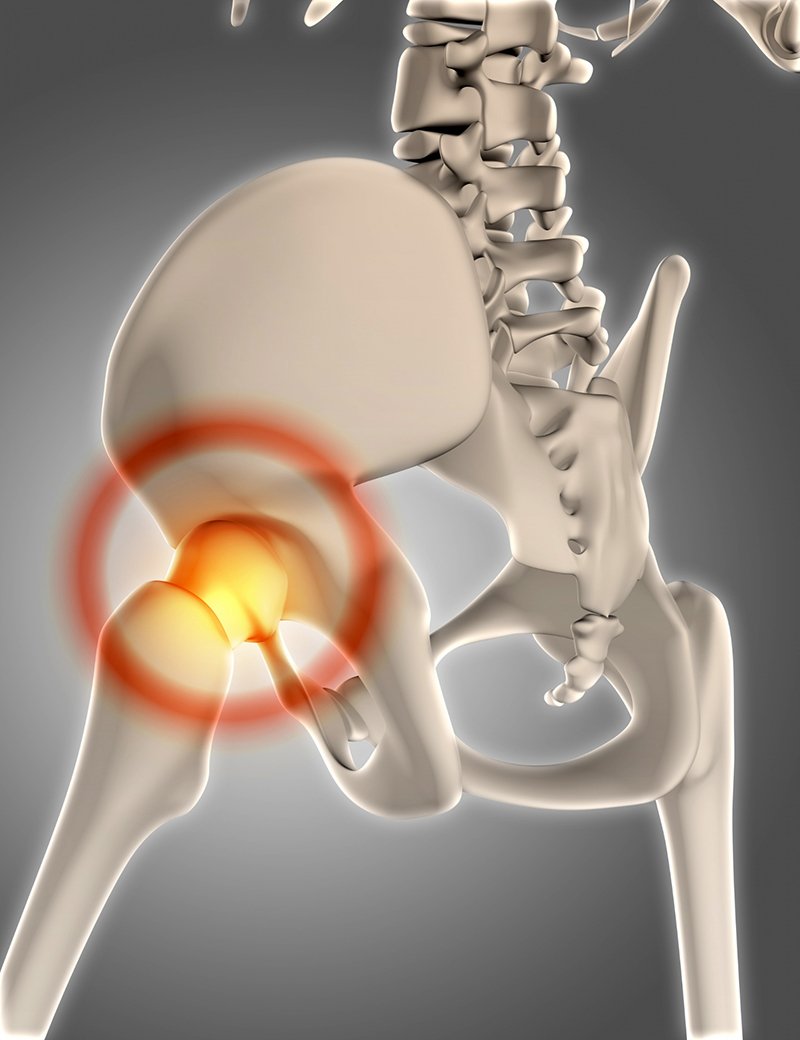

Advanced Hip Replacement for Pain Relief and Improved Mobility : Total Hip Replacement (THR) is a highly successful surgical procedure that relieves chronic hip pain, restores joint function, and improves overall quality of life. It is commonly recommended for patients with severe hip arthritis, hip joint damage, or fractures who have not found relief through non-surgical treatments..

Total hip replacement, also known as hip arthroplasty, involves removing the damaged portions of the hip joint and replacing them with an artificial implant. The damaged hip socket is fitted with a prosthetic cup, and the femoral head is replaced with a metal or ceramic ball attached to a stem, allowing smooth and pain-free movement.

Hip joint damage due to arthritis, injury, or avascular necrosis